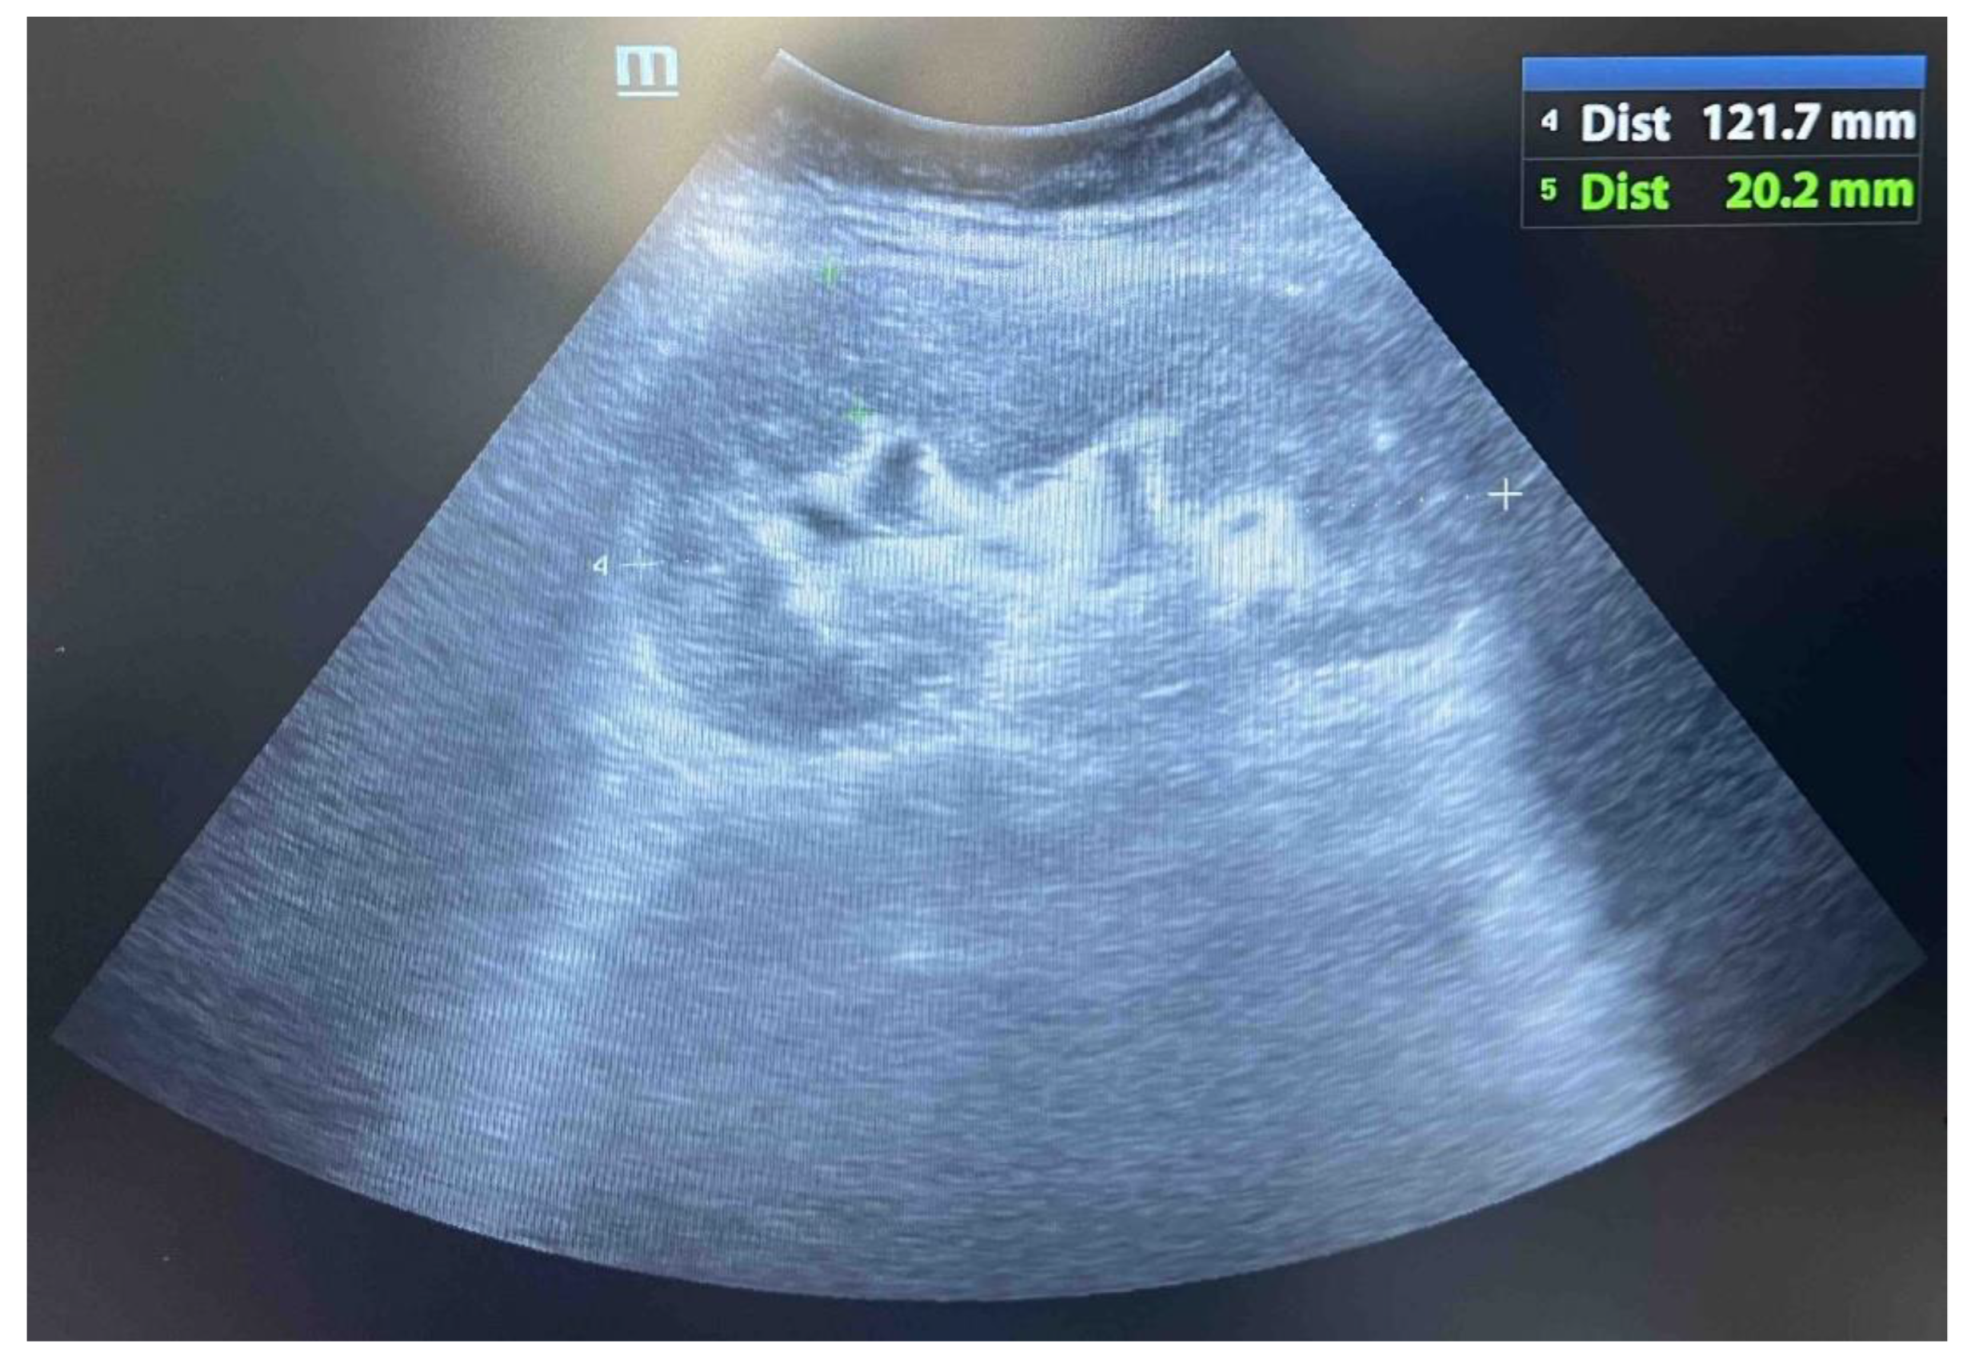

During hospitalization, an ultrasound of the transplant kidney was preformed and after the registered three infiltrative circular lesions isoechoic with parenchyma, a CT scan was also performed using CT-GE Medical Systems, LCC, Revolution HD, Belgrade, Serbia, revealing three lesions in the transplanted kidney, a larger lesion in the body of the pancreas, and additional lesions in the native kidneys (Figure 1, Figure 2 and Figure 3). Additionally, a lesion was identified in the medial lobe of the right lung adjacent to the sixth rib cartilage.

Figure 1. Ultrasound image of transplant kidney with lymphoma.